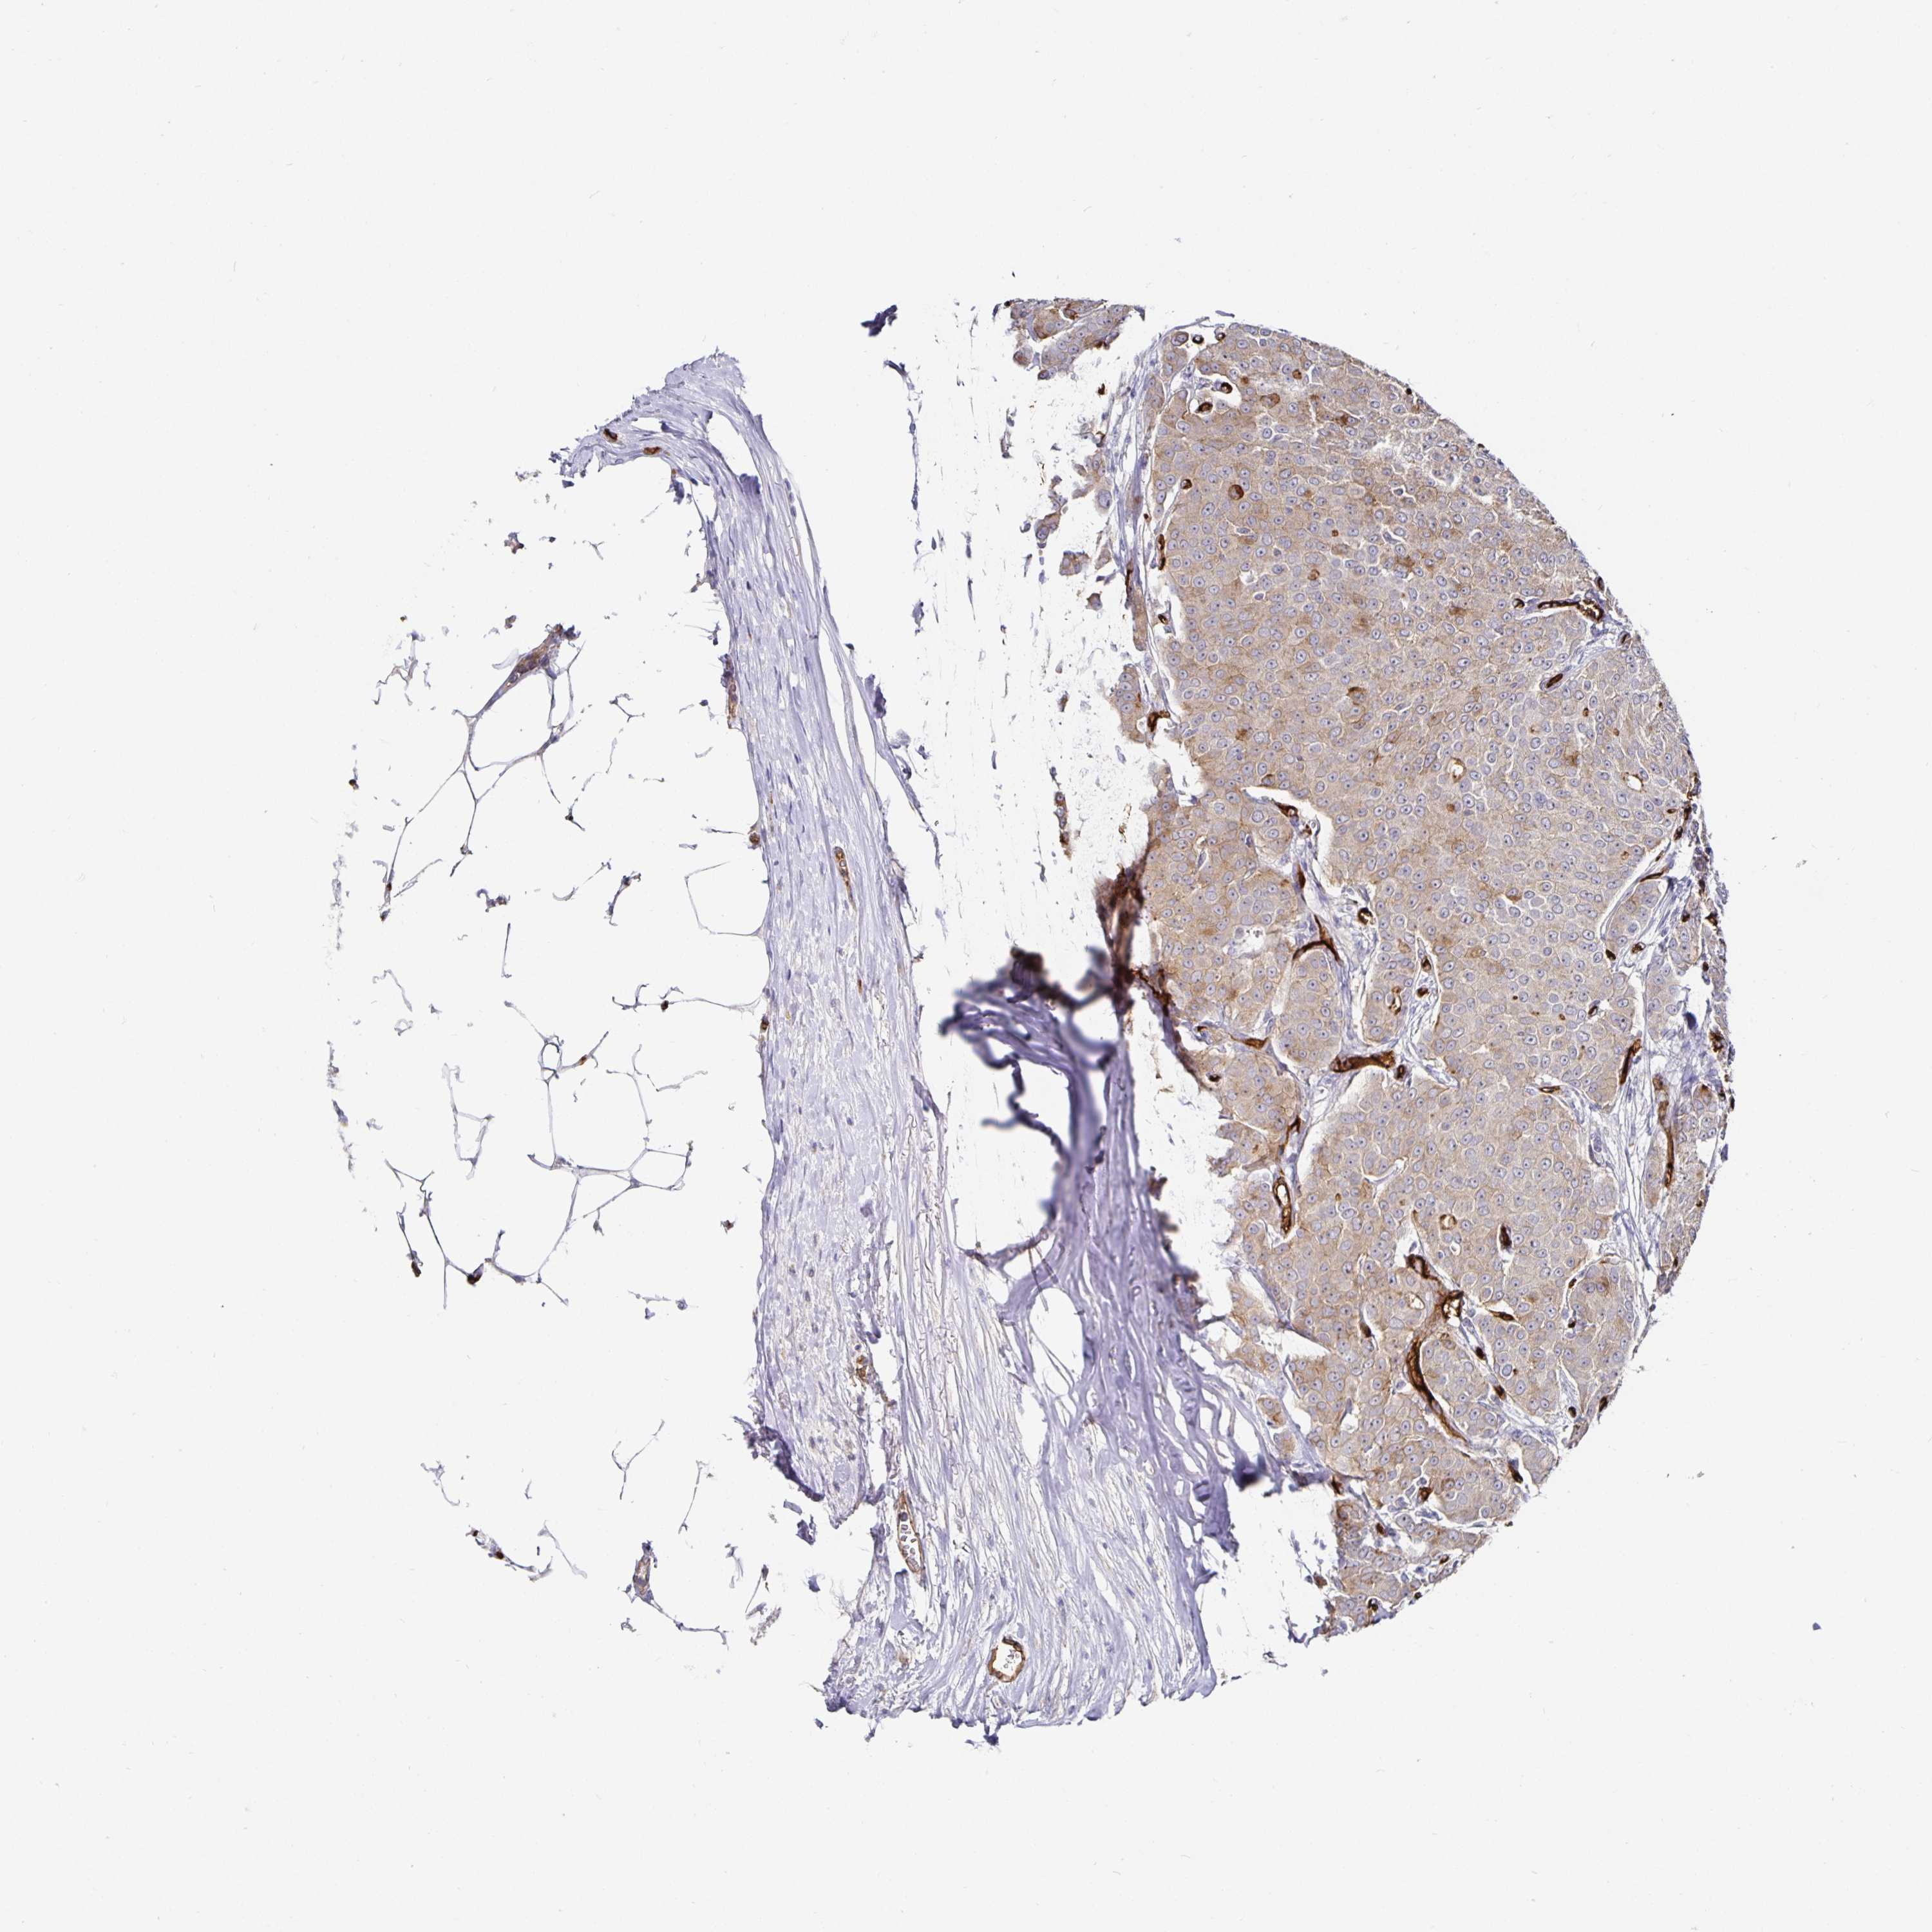

CANCER BREAST CANCER Show tissue menu

BRCA TCGA BRCA VALIDATION PROTEIN EXPRESSION